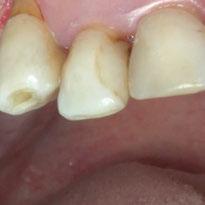

2. Exploración de tejidos blandos

El paciente presentaba biotipo periodontal grueso, con márgenes asimétricos, con recesiones gingivales a nivel de 11 y 13 y pérdida de tejidos blandos interproximales.

3. Exploración de tejidos duros

En la exploración radiográfica (OPG, CBCT) observamos la existencia de pérdida ósea interproximal, lesión apical a nivel de la raíz mesial del 27 y el cordal del primer cuadrante incluido y neumatización sinusal del primer y segundo cuadrante.

En el CBCT observamos pérdida ósea posterior superior debida a la neumatización de los senos maxilares izquierdo y derecho. También podemos observar disponibilidad ósea apical suficiente en dientes antero-superiores para la realización de una Implantología inmediata y corticales vestibulares y palatinas conservadas.